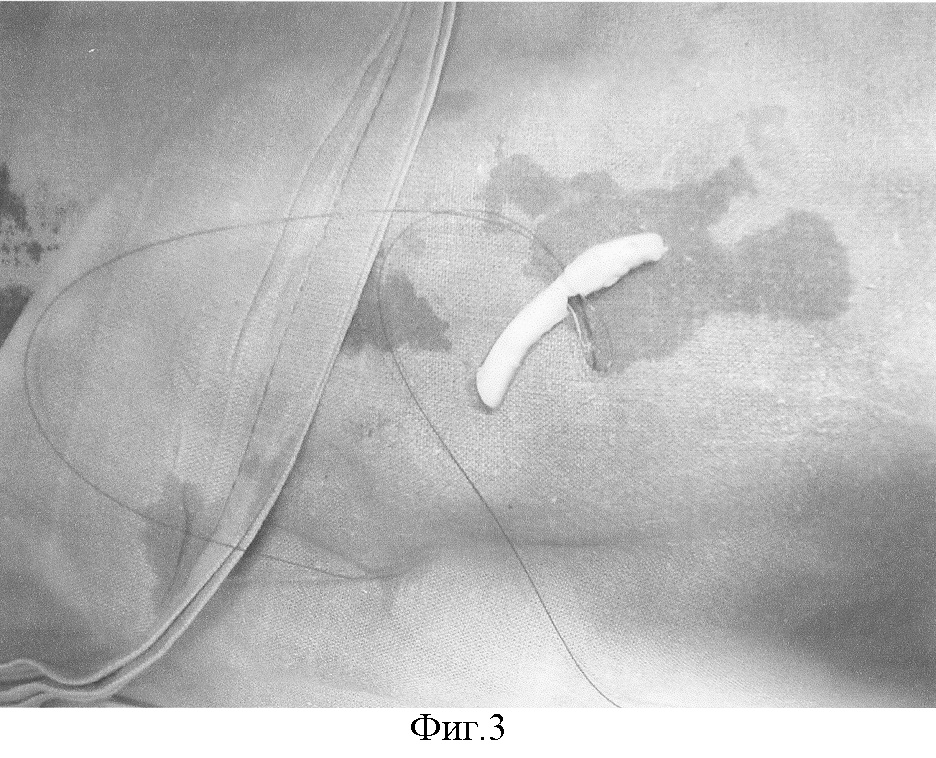

Фиг.3 – в средней части фрагмента хряща выполнена клиновидная резекция с сохранением одной из поверхностей. Этап наложения швов в области резекции для формирования дуги.